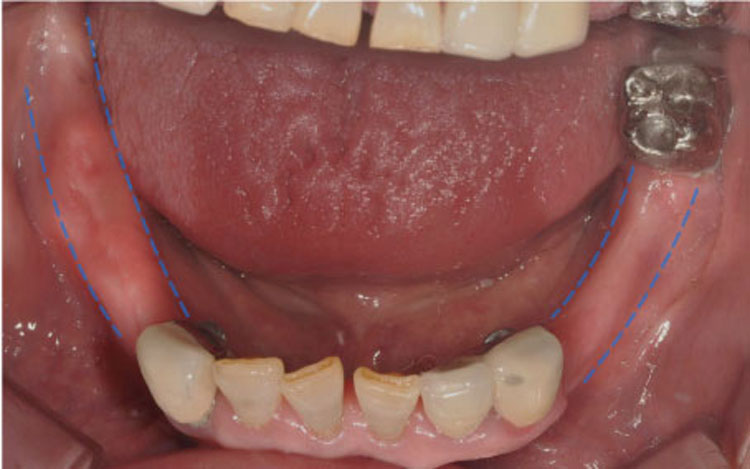

[임플란트] 뼈 이식

치료전 : 2019-11-13